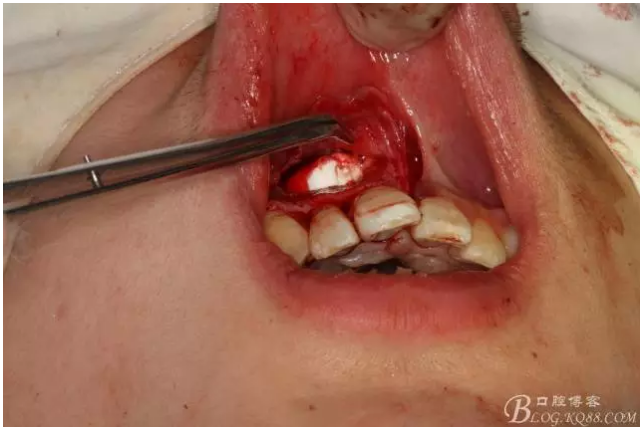

圖4.摘除囊壁后形成的巨大骨腔

圖5.清理骨腔,可以看到12的根尖暴露在骨腔內(nèi)。

圖6.超聲骨刀切除根尖3mm。